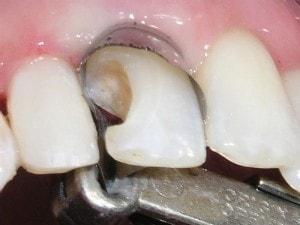

Caries in incisor teeth

Decay in teeth #'s 7, 8, and 10

Restoration complicated by overlap

Carles removed

Enamel tapered on both preps. Enamel taper includes the entire labial of tooth #7. Many call this an apple core prep.